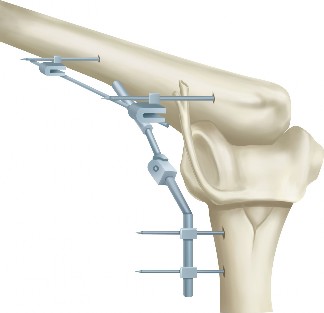

The patient’s symptoms fail to improve after 6 months of conservative management, including activity modification, physical therapy (PT), nonsteroidal anti-inflammatory drugs, and ultrasound guided injections. The injections provided short-term relief. Radiographs and a three-dimensional CT scan were obtained. The patient had an anterior “horn-like” projection at the superomedial angle of the scapula. Surgical intervention is planned using a modified mini-open approach with arthroscopy-assisted bursectomy. Portals are placed 3 cm medial to the medial scapular border.

The correct answer is (C). The dorsal scapular artery and nerve travel beneath the rhomboid minor and major muscles approximately 1 to 2 cm medial to the medial scapular border. Portal placement should therefore be located approximately 3 cm medial to the medial scapular border (Fig. 2–80).

Figure 2–80_Reproduced with permission from Warth, RJ, Spiegl UJ, Millet PJ. Scapulothoracic bursitis and snapping scapula syndrome: a critical review of current evidence. _Am J Sports Med 2014 Mar 24. [Epub ahead of print]

Answer A is incorrect because the long thoracic nerve is rarely endangered unless dissection is carried lateral. The suprascapular nerve can be endangered if a portal is placed superior to the scapular spine. The deep branch of the transverse cervical artery becomes the dorsal scapular artery. The spinal accessory nerve travels with the superficial branch of the transverse cervical artery, and its branches are at risk if a portal is placed superior to the scapular spine. Scapulothoracic bursitis is usually managed nonoperatively. Nonoperative treatment includes activity modification, NSAIDs, PT, and corticosteroid injections. If symptoms are recalcitrant to conservative management or associated with an osseous or soft tissue mass, surgical intervention is indicated. Arthroscopic, open, or a combined operative approach can be performed. Arthroscopy is more technically demanding, but it does not require postoperative immobilization because the rhomboids and levator scapulae are not transected and reattached to the scapula after partial scapula resection is performed.